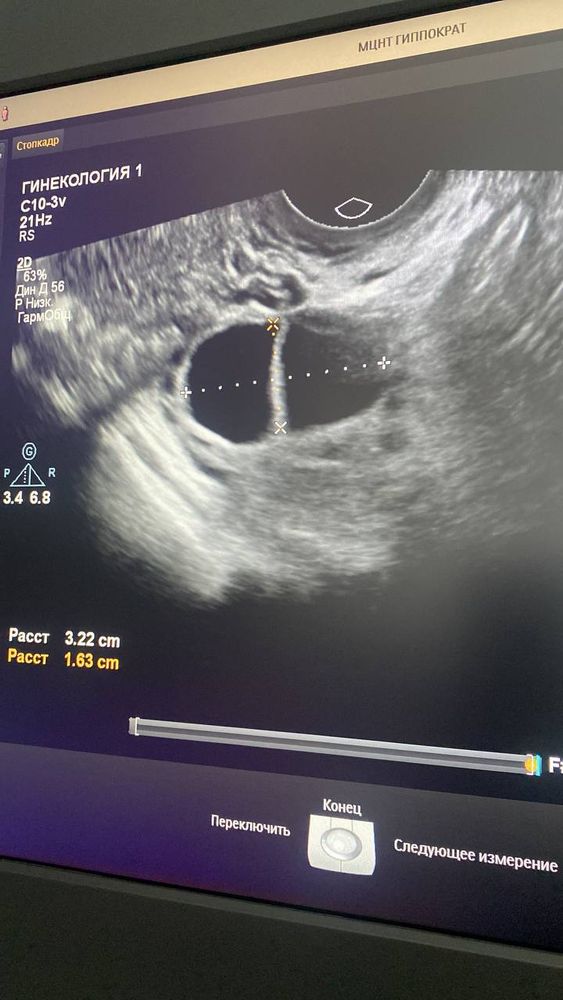

Киста с перегородкой или 2 доминантных фолликула рядом?

Стимулировалась клостилбегитом 50мг, вчера на УЗИ ДФ с перегородкой 24мм, сегодня он уже 35мм (14 дц). Врач сказала что это уже киста, а другой врач сказал что за сутки не мог он так сильно вырасти и на этом УЗИ не понятно, что может быть это 2 фолликула рядом.

На 2 не похоже, они более овальные по форме, если б каждый был самостоятельным.